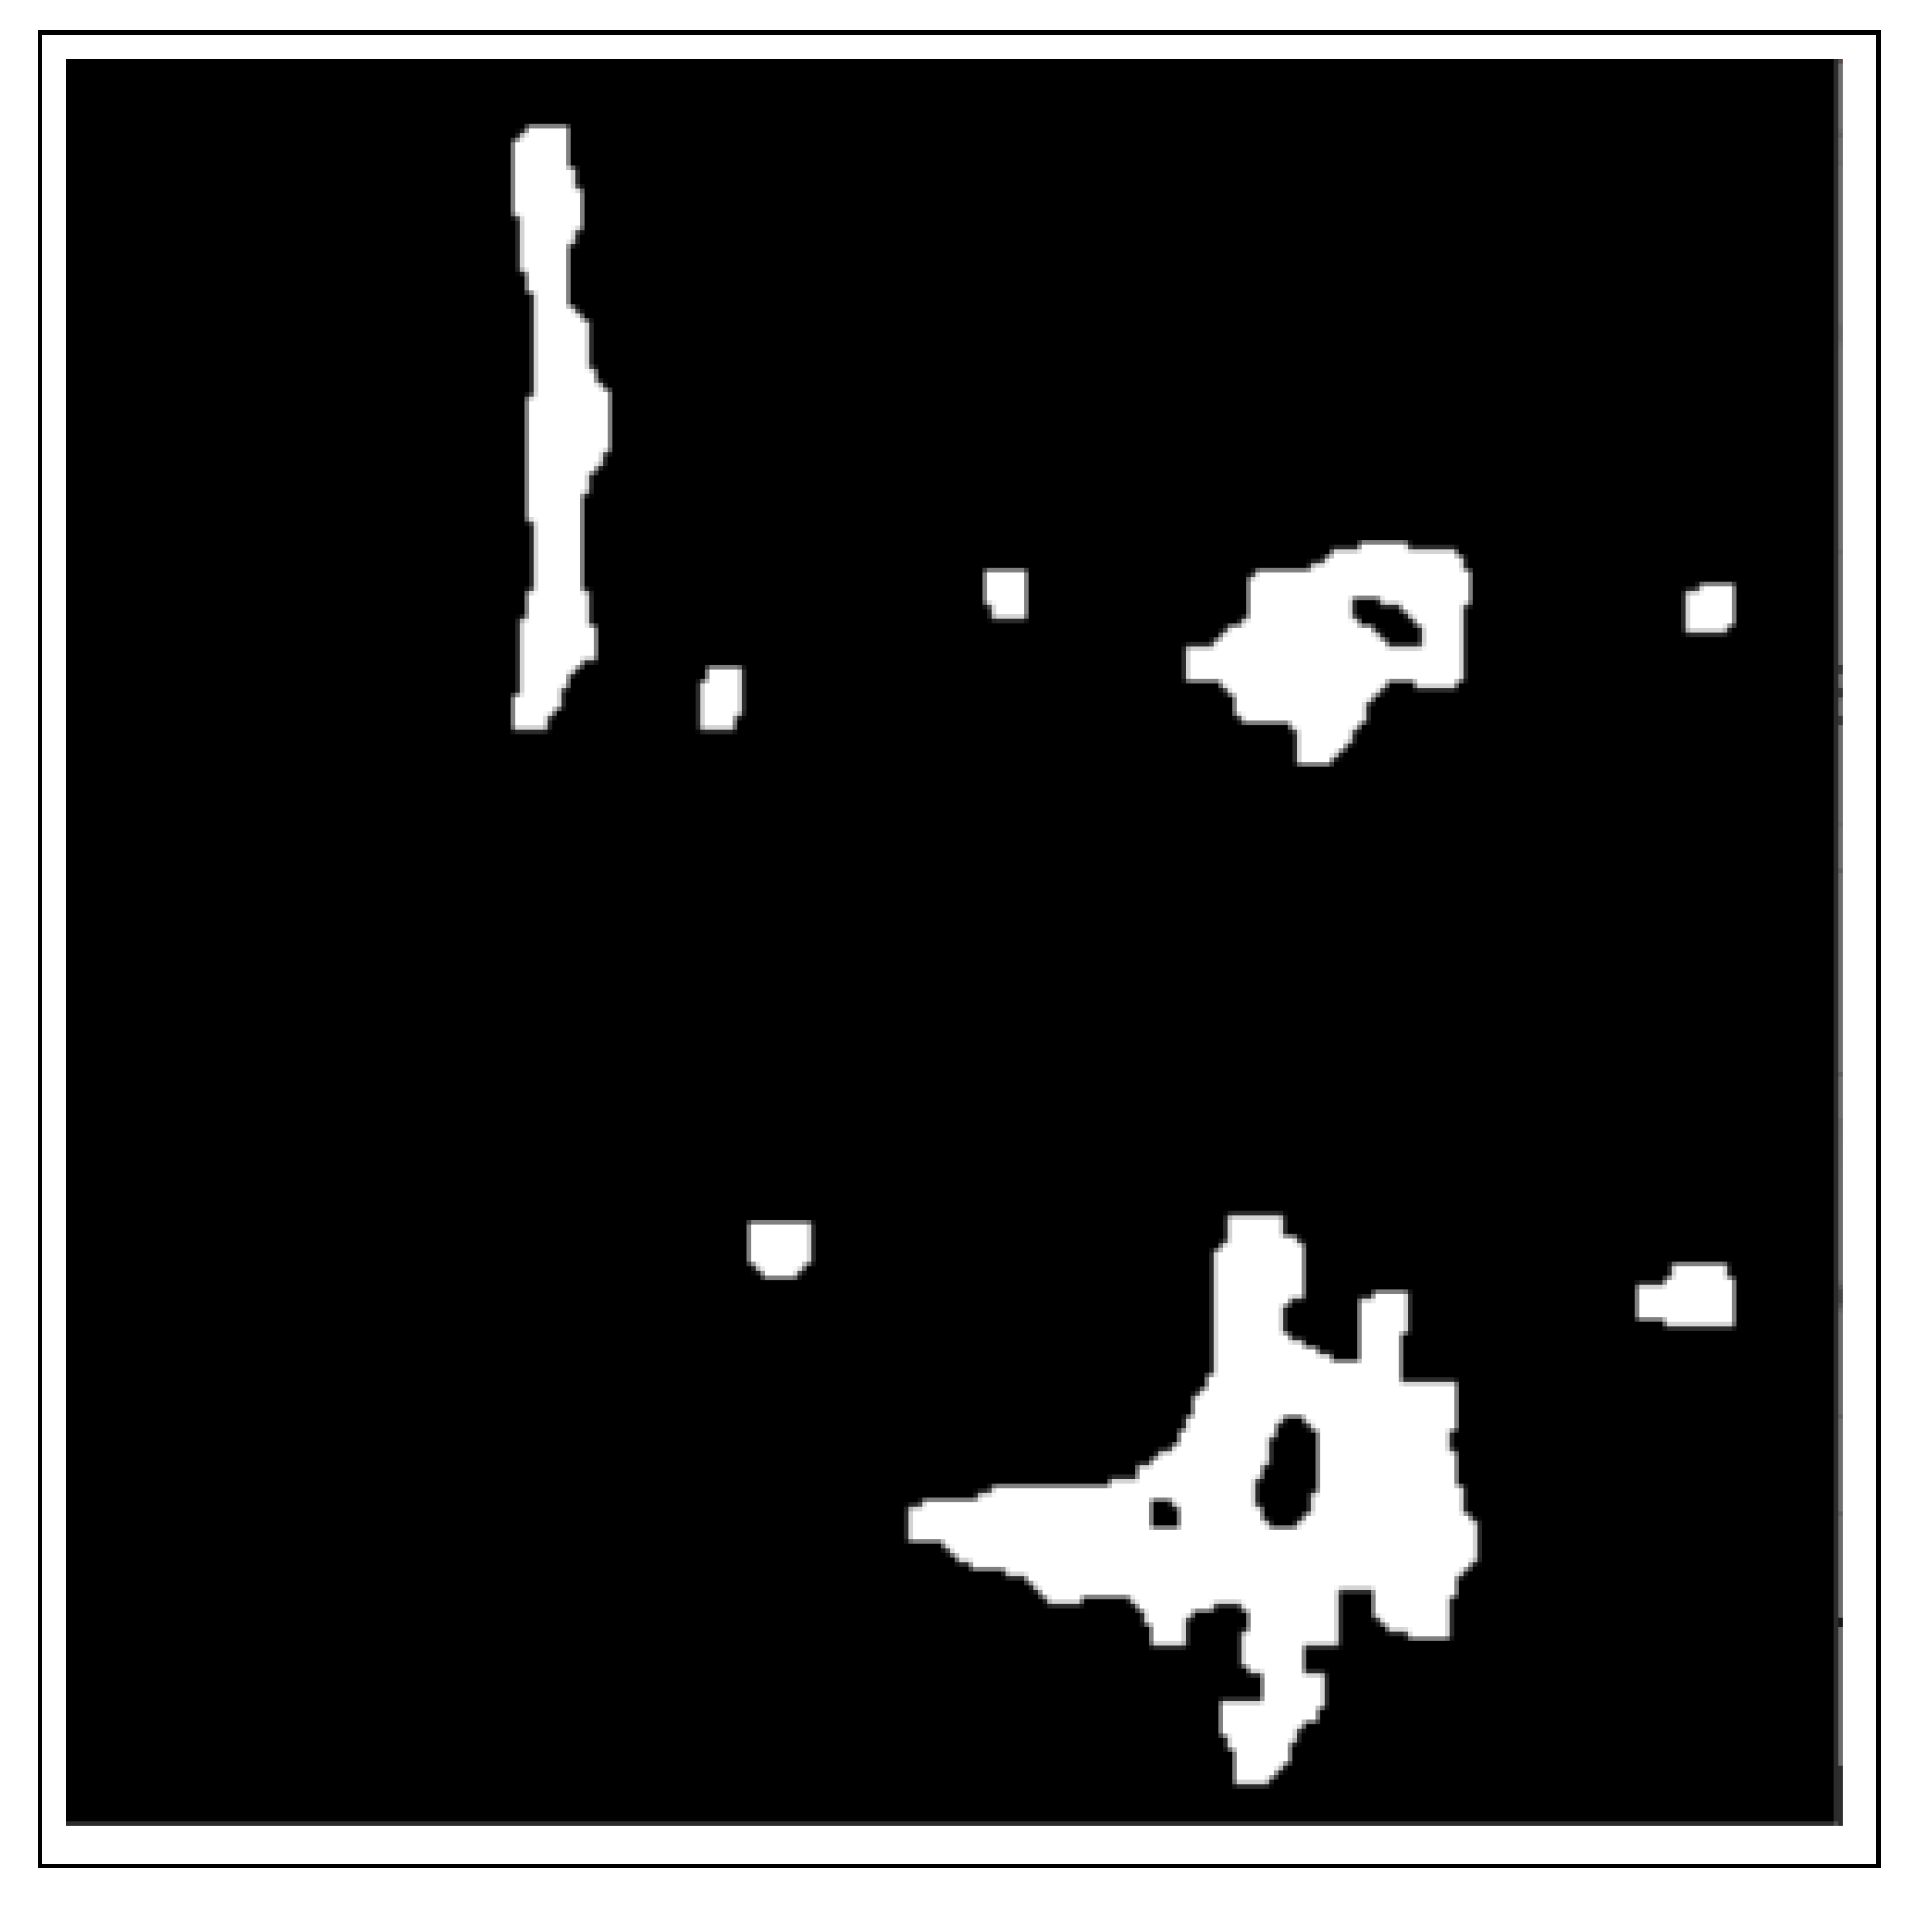

- The use of the connected component analysis method to group components with similar characteristics into binary masks that assist in separating overlapping and non-overlapping objects, thus avoiding over-segmentation.

- The binary masks from the connected component analysis method further aid in addressing the inaccurate segmentation of the image boundaries of intersecting objects, which is common with the active contours method. The proposed method clearly distinguishes the different ROIs from each other, clearly isolating and segmenting the cancerous lesions as visually documented in Section 3 and Section 4.

2.3.1. Connected Component Analysis

2.3.2. Active Contours Segmentation